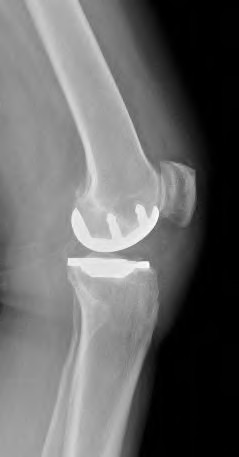

A 72-year-old female presents with progressive left thigh and knee pain for the last year. 5 years ago she sustained a femoral neck fracture treated with the implant seen in Figures A-C (current radiographs). The thigh pain is worse with weight-bearing. C-reactive

protein and erythrocyte sedimentation levels are within defined limits. Which of the following is the most likely cause of her pain?